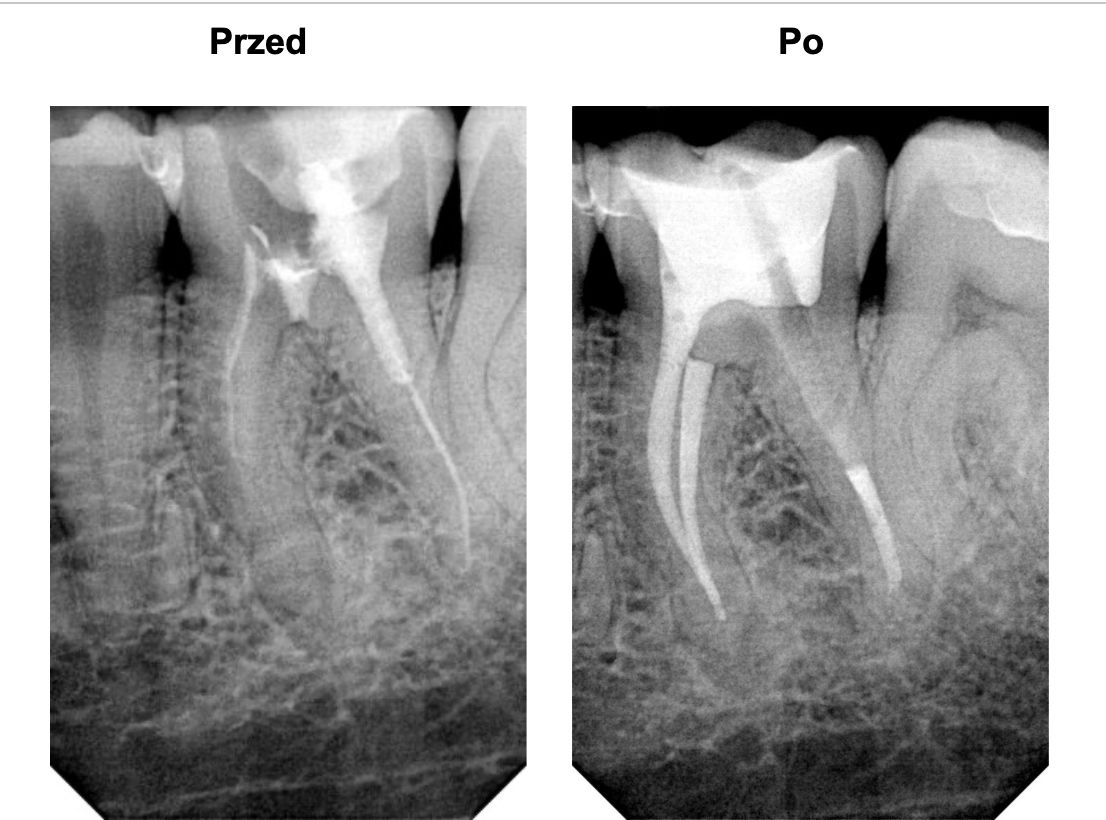

W klinice dostępny jest najnowszy model lasera, który pozwala na osiąganie maksymalnych szans powodzenia leczenia kanałowego.

Od początku swojej drogi zawodowej związana była z jedną z najnowocześniejszych klinik, gdzie uczyła się od wybitnych specjalistów z branży. Swoją praktykę lekarską rozpoczęła zajmując się endodoncją, zdobyła w tej dziedzinie ogromne doświadczenie. Zajmuje się wykonywaniem najbardziej zaawansowanych leczeń endodontycznych, powtórnych leczeń kanałowych oraz usuwaniem złamanych narzędzi i zamykaniem perforacji.

Pracuje zawsze pod mikroskopem, w osłonie koferdamu i zawsze w oparciu o tomografię komputerową, w klinice posiada najnowocześniejszy sprzęt tomograficzny oraz narzędzia maszynowe do leczeń kanałowych.

Doktor uważa, że obraz mówi więcej niż słowa, zapraszamy do zapoznania się z galerią jej prac.